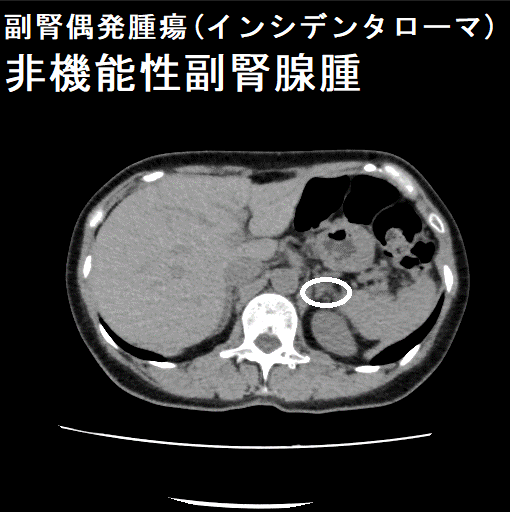

副腎は左右腎臓の上にあるのホルモン分泌臓器。副腎腫瘍はホルモンを作る機能性副腎腫瘍と作らない非ホルモン産生性腫瘍がある。腹部超音波検査やCTで偶然(1-5%、高齢者は10%)副腎腫瘍が発見される(副腎偶発腫瘍:インシデンタローマ)。約75%は副腎腺腫、約50%は非機能性副腎腺腫だが3cm以上なら副腎癌(副腎原発1%/転移性5%)の事がある。骨髄脂肪腫3%。機能性副腎腫瘍はクッシング症候群10%・褐色細胞腫10%・原発性アルドステロン症5%。単純CTでCT値が10HU未満の低吸収値になる副腎腫瘍は脂質を多く含む副腎腺腫。

腹部超音波検査やCTで偶然(1-5%、高齢者では10%)副腎腫瘍を発見される事があり、副腎偶発腫瘍(インシデンタローマ)と呼ばれます。

大阪大学の報告では、副腎偶発腫瘍(インシデンタローマ)の大半(77.0%)はCTで発見され、残りは腹部超音波検査(14.6%)、MRI(4.2%)、PET検査(4.2%)で同定。右側よりも左側に多く、腫瘍の平均直径は21±11mm。73.3%はホルモンを作らない非機能性副腎腫瘍。機能している腫瘍を有する患者は、機能していない腫瘍を有する患者よりも有意に若く、腫瘍の直径が大きかった。

非機能性副腎皮質腺腫が3cm以上の場合、副腎癌(副腎原発1%/転移性5%)の事があります。